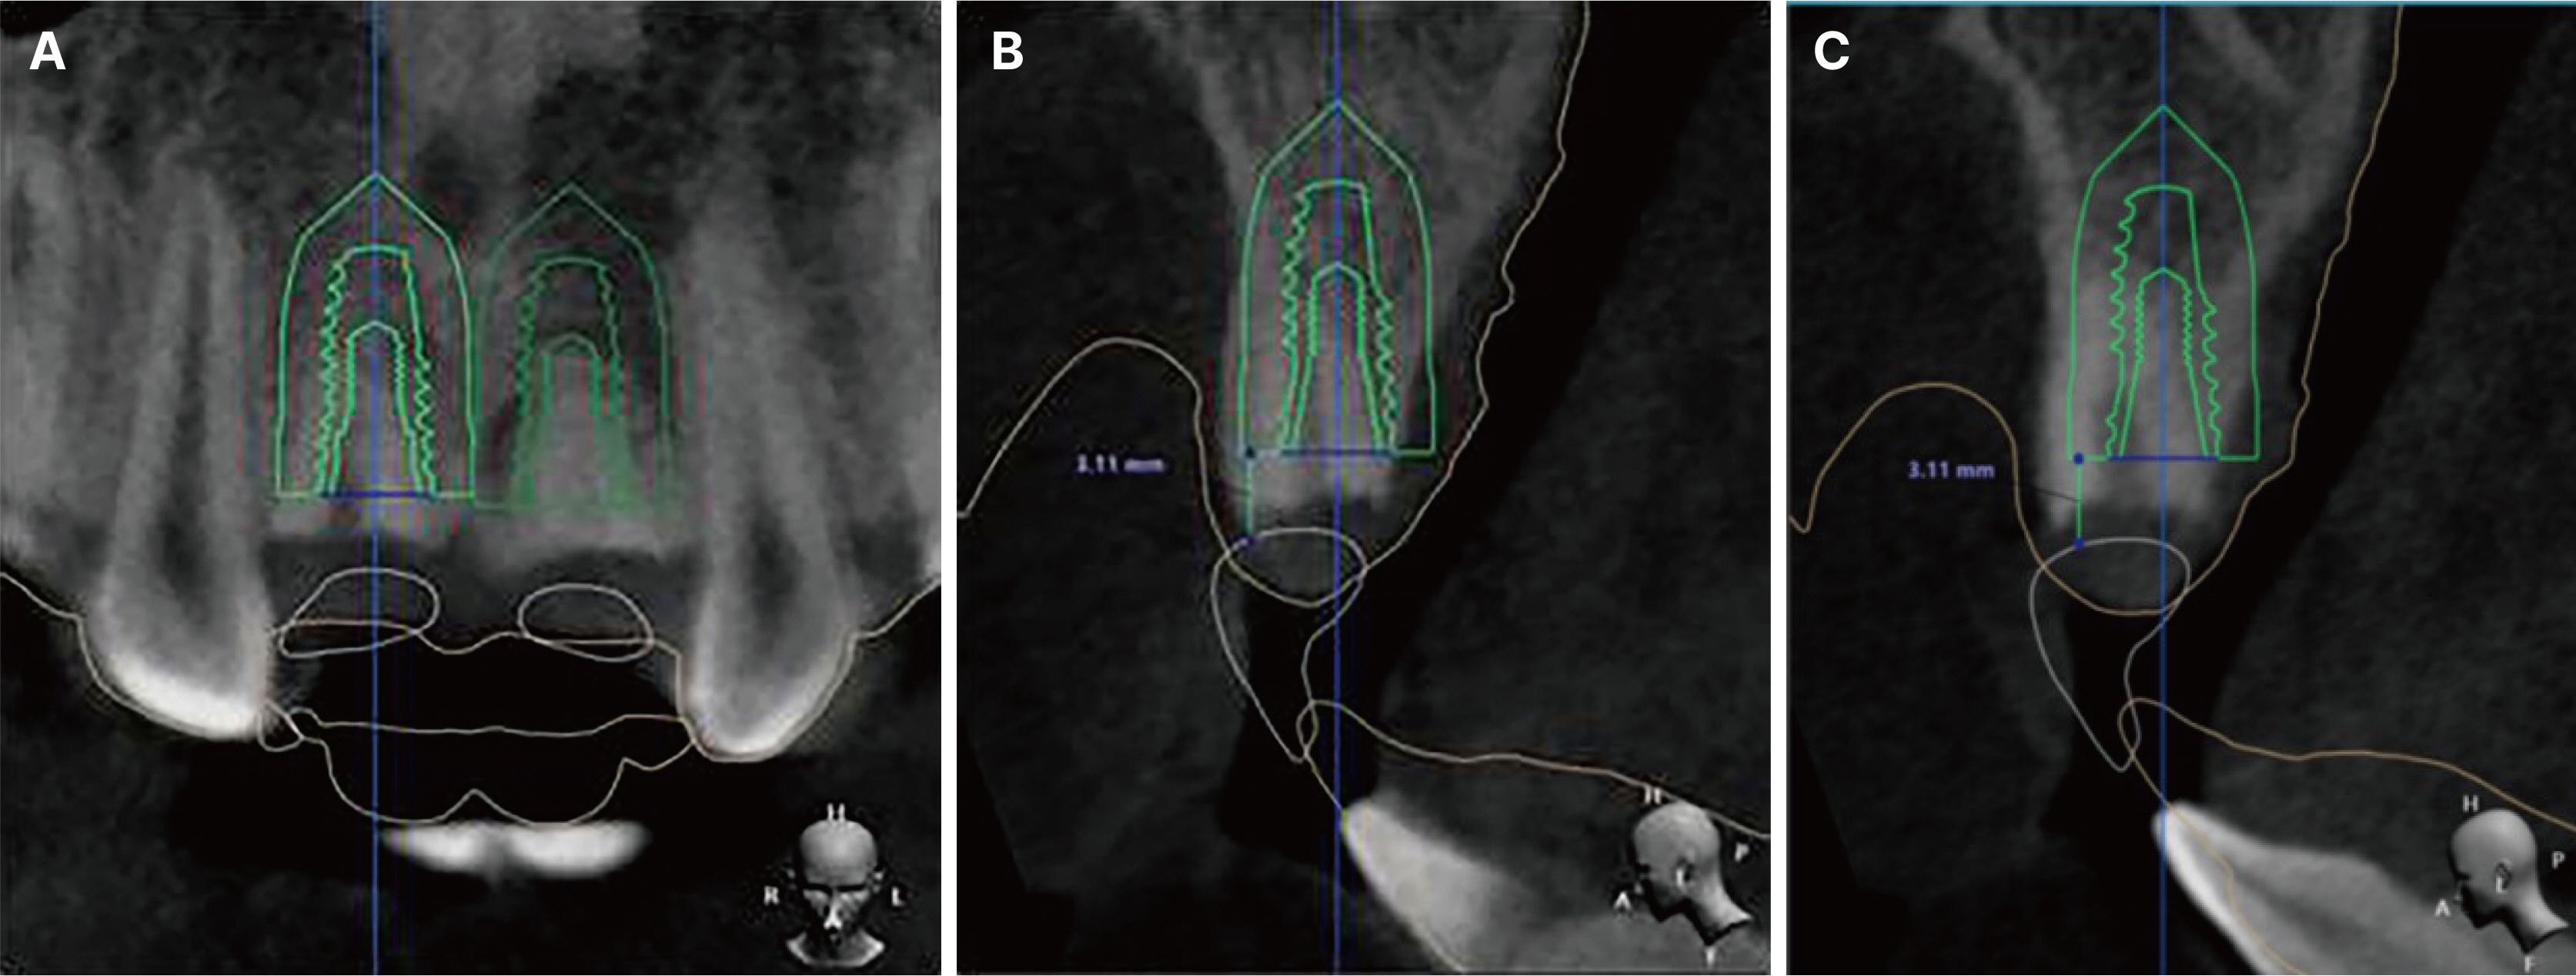

- Immediate implant placement and immediate loading in the anterior maxilla is an effective approach to rapidly address aesthetic demands. To achieve successful outcomes, bone quality, soft tissue condition, and accurate implant positioning are essential factors. For optimal results, procedures such as bone augmentation, precise implant placement, and, when necessary, soft tissue grafting should be considered. Furthermore, provisional restoration play a crucial role in achieving the desired appearance of prosthetic restorations and improving the aesthetics of the soft tissue. By performing soft tissue molding through provisional restoration, an ideal emergence profile can be established, which can be subsequently transferred to the final prosthesis, leading to a functional and aesthetically pleasing restoration. This approach aims to optimize the aesthetic outcomes in the anterior region while preserving the natural contours of the peri-implant soft tissue. In this case, a patient requiring extraction of maxillary anterior tooth underwent immediate implantation and alveolar bone grafting using a guide fabricated in advance from CT data. The patient received a provisional restoration on the same day. Subsequent steps included transitioning from the provisional prosthesis to the definitive prosthesis, ultimately achieving an aesthetically pleasing and functional implant restoration. We report this case to highlight the successful approach to maxillary anterior implant rehabilitation.